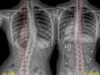

أبريل 1, 2025 هل يسبب اعوجاج العمود الفقري ارتجاع المريء؟ إليك العلاقة وطرق تخفيف الأعراض بسهولة… scoliosis, اعوجاج العمود الفقري, الجنف لا يوجد تعليق 149 المشاهدات هل يسبب اعوجاج العمود الفقري ارتجاع المريء؟ يعاني الكثير من المرضى، وخاصة المراهقين والبالغين، من مشكلتين صحيتين تبدوان في الظاهر غير مرتبطتين: اعوجاج العمود الفقري وارتجاع المريء. لكن المفاجأة أن هناك علاقة طبية بين